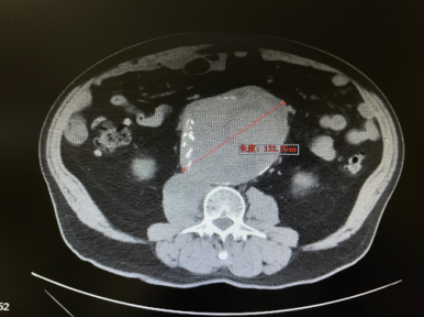

11月4日晚,一名76岁的老人因腰背部剧烈疼痛,来到北京天坛医院急诊。CT检查发现,老人腹腔里有一个直径达13厘米的巨大腹主动脉瘤,瘤体已经出现先兆破裂,瘤颈极度扭曲,一旦出血继续进展,会引起失血性休克威胁患者生命,情况十分危急。患者年迈,基础条件很差且患有慢性阻塞性肺疾病及冠心病,曾接受过冠状动脉搭桥手术,开放手术风险极高。值班医生立即将情况汇报给血管外科主任沈晨阳,沈晨阳第一时间赶回医院,并指示值班医生马上联系手术室、麻醉科、重症医学科、输血科等相关科室,做好急诊手术准备。